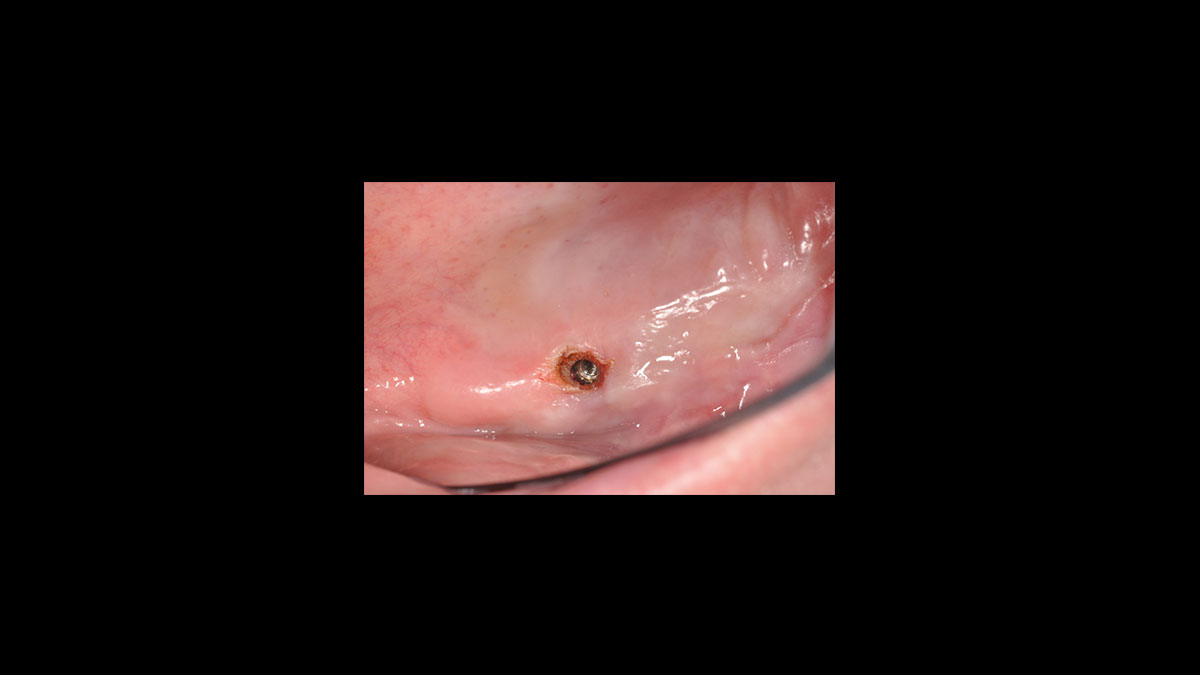

Operculectomía

• Operculectomía